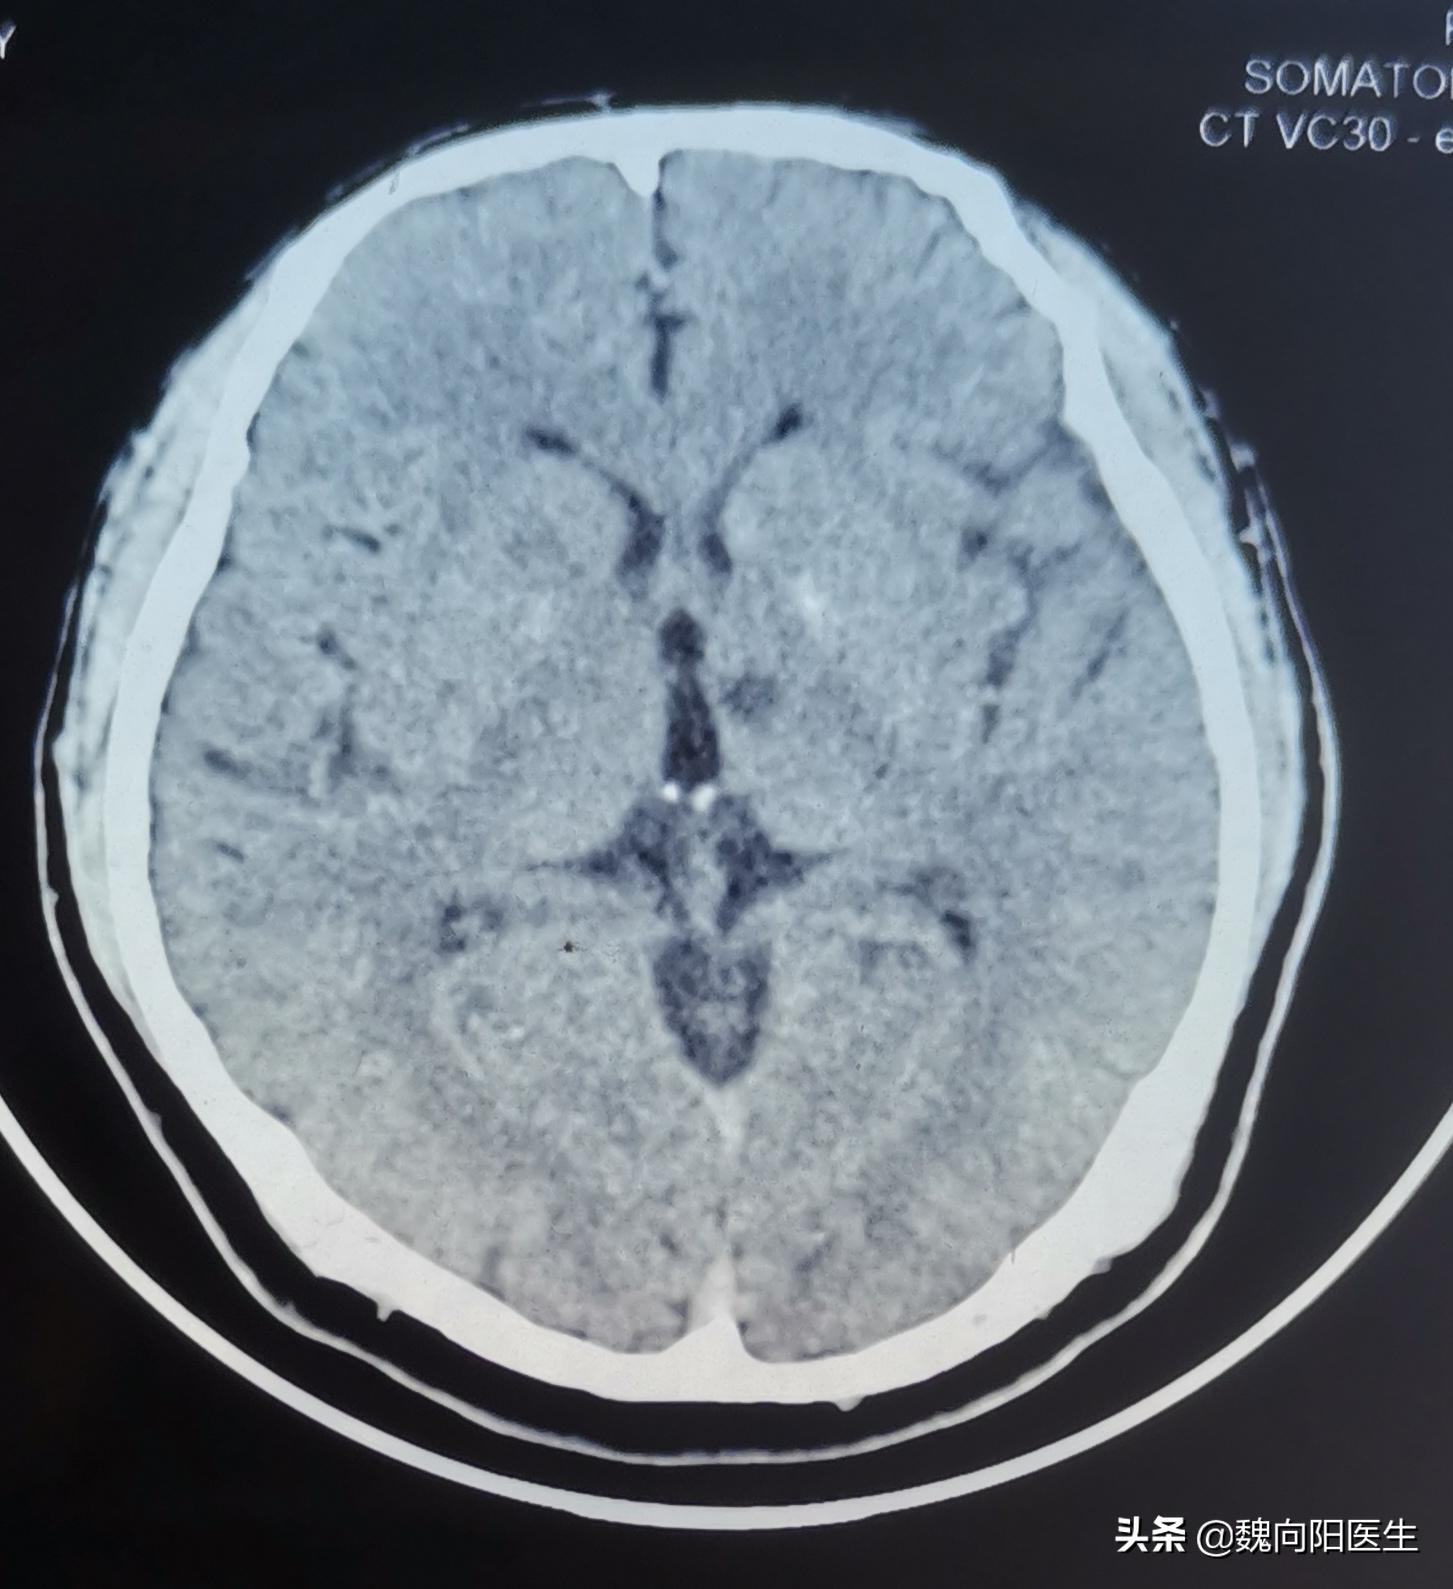

腔隙性脑梗死定义

腔隙性脑梗死往往是在查头CT或头MRI检查时,无意中发现的。

腔隙性脑梗死:是脑穿支小动脉闭塞引起的深部脑组织较小面积的缺血性坏死,一般<15mm圆形或椭圆形软化灶。好发部位为基底核区和丘脑区,也可发生于脑干、小脑等区域,单发或多发。不要轻视轻型脑梗死和TIA